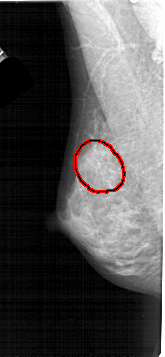

FILE: A_1446_1.LEFT_MLO.OVERLAY

TOTAL_ABNORMALITIES 1

ABNORMALITY 1

LESION_TYPE CALCIFICATION TYPE AMORPHOUS DISTRIBUTION SEGMENTAL

ASSESSMENT 2

SUBTLETY 3

PATHOLOGY BENIGN

TOTAL_OUTLINES 1

BOUNDARY